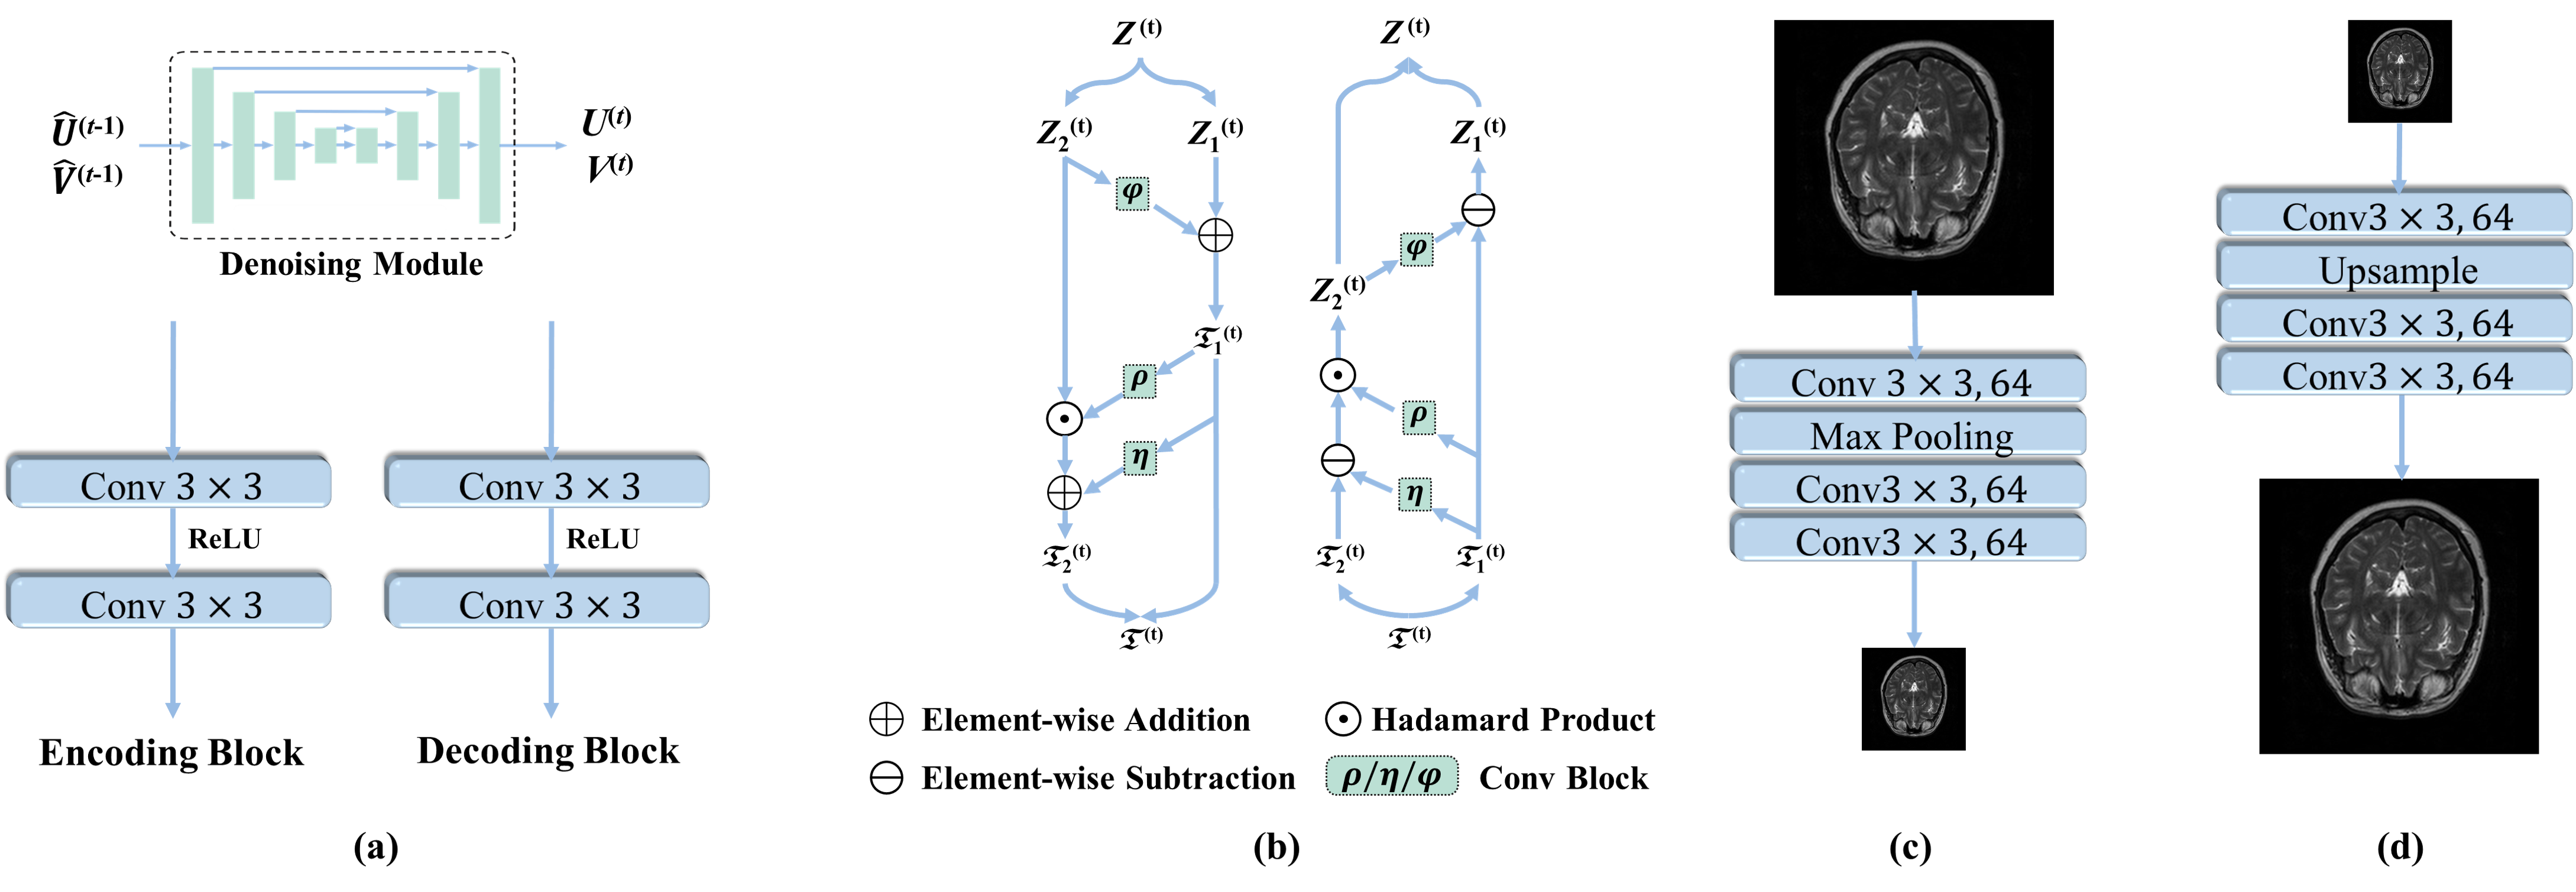

As shown in Fig. 1, the intermediate estimates and are fed into the proximal operator after weighting with the intermediate estimate for further refinement. In this paper, we have adopted a variant of U-net as the backbone of the deep denoising module. Other more effective networks for medical image denoising can be also adopted. The U-net denoising network consists of an encoder and a decoder. As shown in Fig. 2(a), the encoder consists of four encoding blocks, which contain two convolutional layers with kernels and ReLU nonlinearity. Corresponding to the encoder, the decoder also consists of four decoding blocks, which contain two convolutional layers with kernels and ReLU nonlinearity. Instead of predicting the refine auxiliary various directly, we enable the denoising module to predict the residual by adding a skip connection from the input to the output. To reduce the number of network parameters and the effect of overfitting, we opt to enforce all denoising modules sharing the same network parameters.

As a result, we design cross-modal transform modules using the principle of invertible neural networks (INNs). INNs have been adopted in various inference tasks and achieved excellent performance due to their flexibility (Kingma et al., 2016; Lu et al., 2021). We formulate an INN architecture design to serve as cross-modal transform operation. It consists of two pixel shuffling layers (Dinh et al., 2016) and several INN blocks. As shown in Figure 2(b), relevant invertible modules are embedded in the cross-modal transform module.

For the t-th stage, given an evaluation HR MRI () to be refined, we first put it to one pixel shuffling layer for changing dimension, then pass through several INN blocks to execute the cross-modal transform function, and finally restore the original dimension through the other pixel shuffling layer.

For the forward operation, one pixel shuffling layer executes dimension addition first. Then the input () is divided into () and () along the channel axis, and the corresponding cross-modal transform output is and (two components of ). This process corresponds to the operation of cross-modal transform matrix , in which an INN block can be expressed as :

| (21) |

where , and are arbitrary functions, is Exponential functions, and is the Hadamard product.

The design of the reconstruction module corresponds to the update of intermediate evaluated as described in Eq. 16. With the output of denoising modules (, ), the evaluated HR image , the LR MRI and the guide image , we can reconstruct the updated image . The architecture of the reconstruction module is shown in Fig. 1 and Eq. 16, which still involve the degradation operations ( and ). The pair of operation and can be implemented by up-sampling and down-sampling layers for modeling capability.

The operators and are simulated using a convolution network layer respectively. Specifically, is simulated by a network called down-sampling-blocks () consisting of a convolutional layer with kernels and 64 channels, one max pool layer to decrease the spatial resolution, and two convolutional layers with kernels for reprojection to the original dimension (as shown in Figure 2(c)). Similarly, the is simulated by a network call Up-sampling-blocks () consisting of a convolutional layer with kernels and 64 channels, and one upsample layer to increase the spatial resolution and two convolutional layers with kernels for reprojection to the original dimension as shown in Figure 2(d).